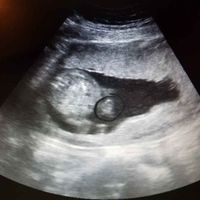

Hola chicas!! Me he decidido a abrir este debate porque veo que muchas os acercáis a mamis julio a preguntarme por el sexo. No soy gine ni nada de eso, eh? Y os aviso de que hay margen de error, pero...